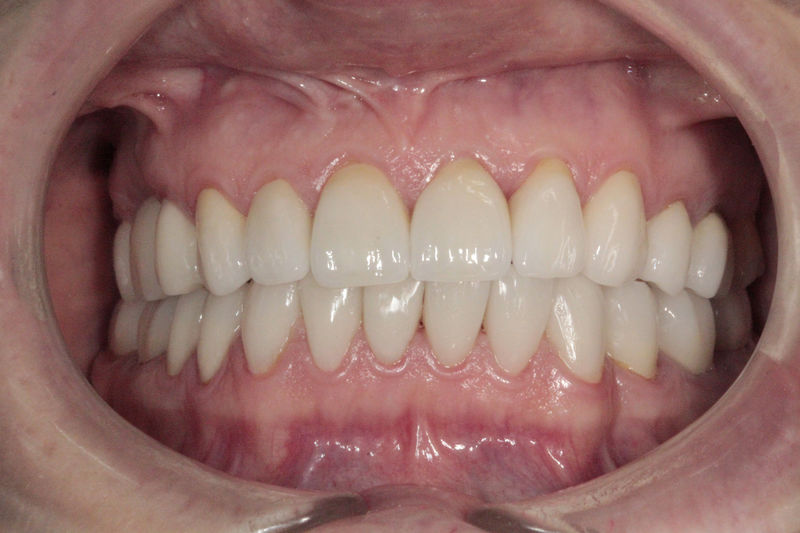

Implantes, ortodoncia y coronas.